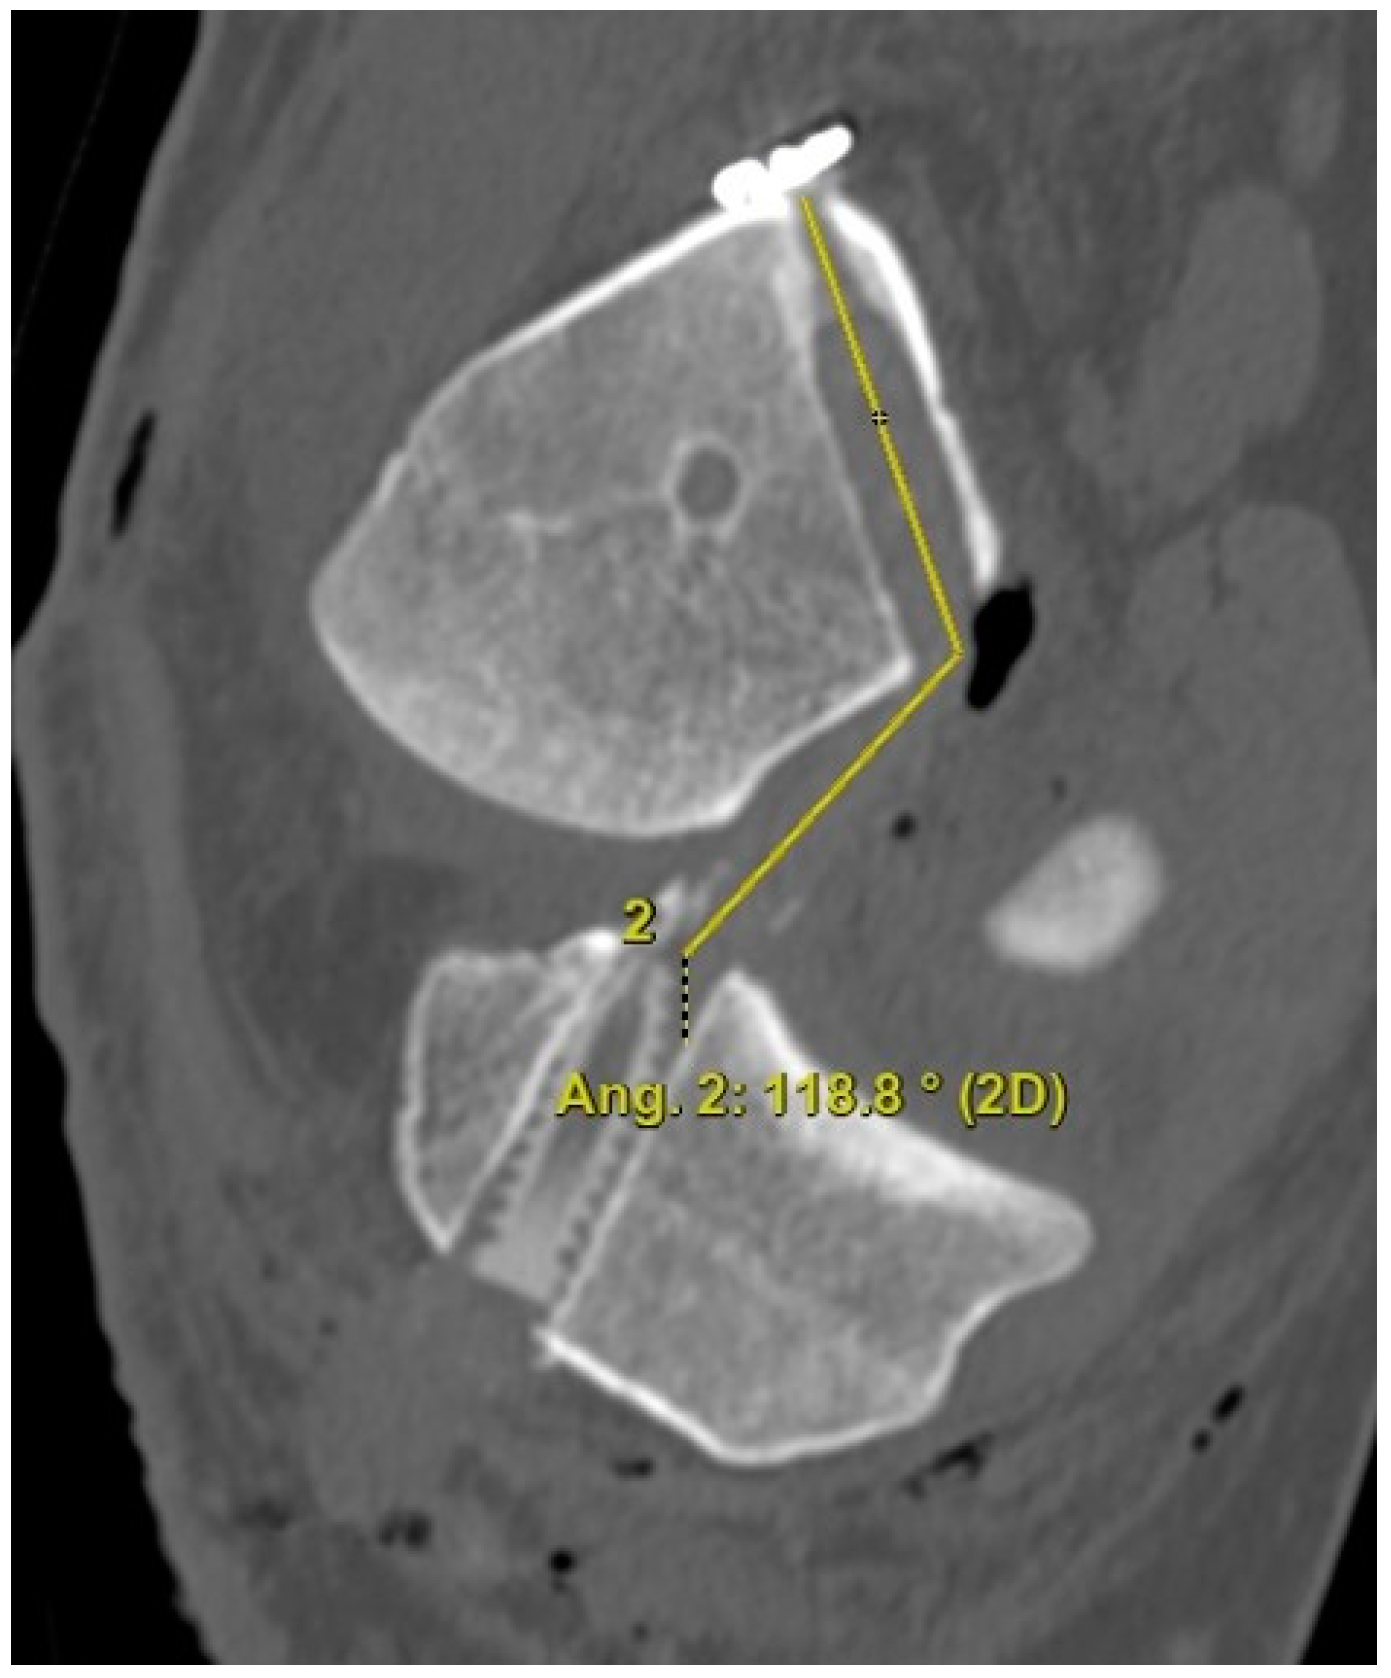

The 3D CT scans were imported into 3D software (AW Sever 3.2 PACS system, GE Healthcare; Chicago, IL, USA) for the assessments of the femoral graft bending angle and femoral tunnel length. The femoral graft bending angle was defined as the angle formed by the longitudinal axis of the femoral tunnel and the line connecting the intra-articular aperture of the tibial tunnel and the intra-articular aperture of the femoral tunnel (Figure 3). The femoral tunnel length was defined as the distance between the center of the extra-articular aperture of the femoral tunnel and the center of the intra-articular aperture of the femoral tunnel in a plane where the entire femoral tunnel could be viewed (Figure 4). Posterior wall breakage of the femoral tunnel was also checked.

Figure 4.

The femoral tunnel length is defined as the distance between the center of the extra-articular aperture of the femoral tunnel and the center of the intra-articular aperture of the femoral tunnel.

Regarding the femoral tunnel location, it was located at 29.7 ± 4.4% in the posterior to anterior (deep to shallow) direction and at 24.1 ± 5.9% in the proximal to distal (high to low) direction. The mean femoral graft bending angle was 113.9 ± 5.7°, and the mean femoral tunnel length was 35.2 ± 3.1 mm (Table 3). There were no cases of a femoral tunnel length <30 mm because the guide pin was redirected for those <30 mm while making the knee joint flexion to approximately 110°. Posterior wall breakage was observed in five patients (8.3%). In the MRIs, the mean coronal graft inclination was 69.2 ± 4.7°, and the mean sagittal graft inclination was 52.4 ± 4.6° (Table 3). The mean posterior tibial slope 241 was 7.9 ± 3.5, and there was no posterior tibial slope of more than 12°.